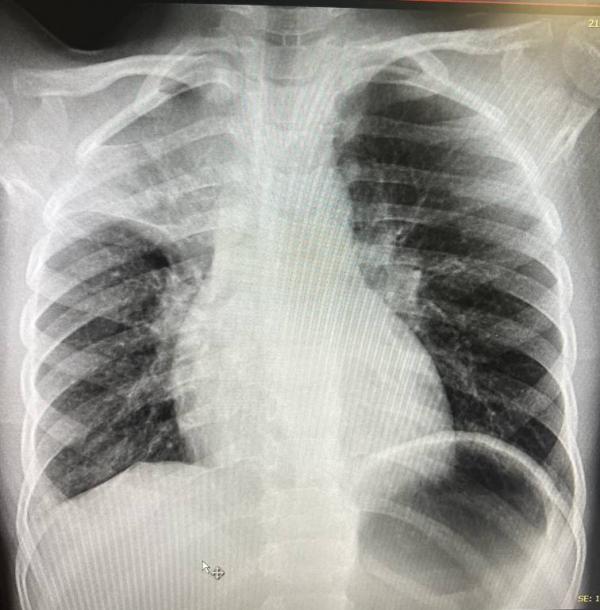

post image 1

В Тушинской больнице на рентгене подтвердили пневмонию, да еще и с "бонусом" в виде воздуха в средостении (на счастье, в небольшом количестве). Муж решил остаться лечить его там...

Но тут было другое. Из-за решения уйти под расписку до окончания лечения, Богдану решили повторить рентген (он как раз на картинке). Там увидели ателектаз верхней доли справа и... Предложили провести санационную бронхоскопию 🙈

Вчера (спустя неделю) мы сходили еще разок на рентген - динамика хорошая))